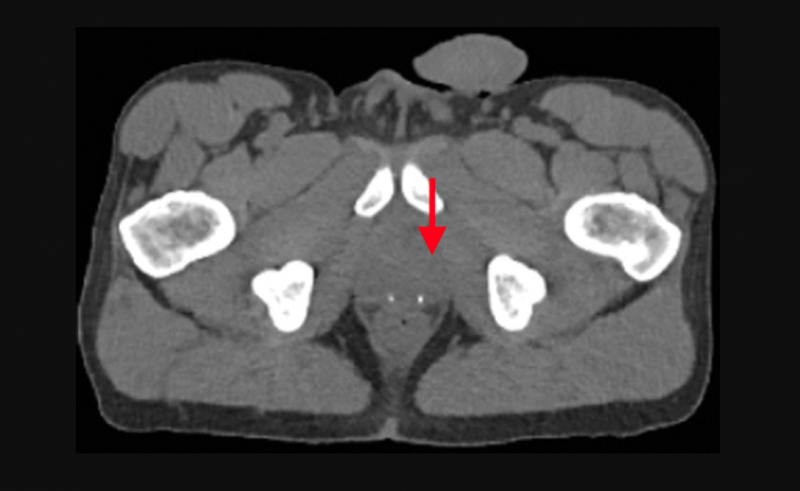

Axial fused PET/CT image shows intense uptake (arrowhead) in the deep pelvis corresponding to the left lobe of the prostate in a 62-year-old with a history of prostate cancer treated with radiation therapy. The CT scan does not show the tumor. Image courtesy of the the Radiological Society of North America.